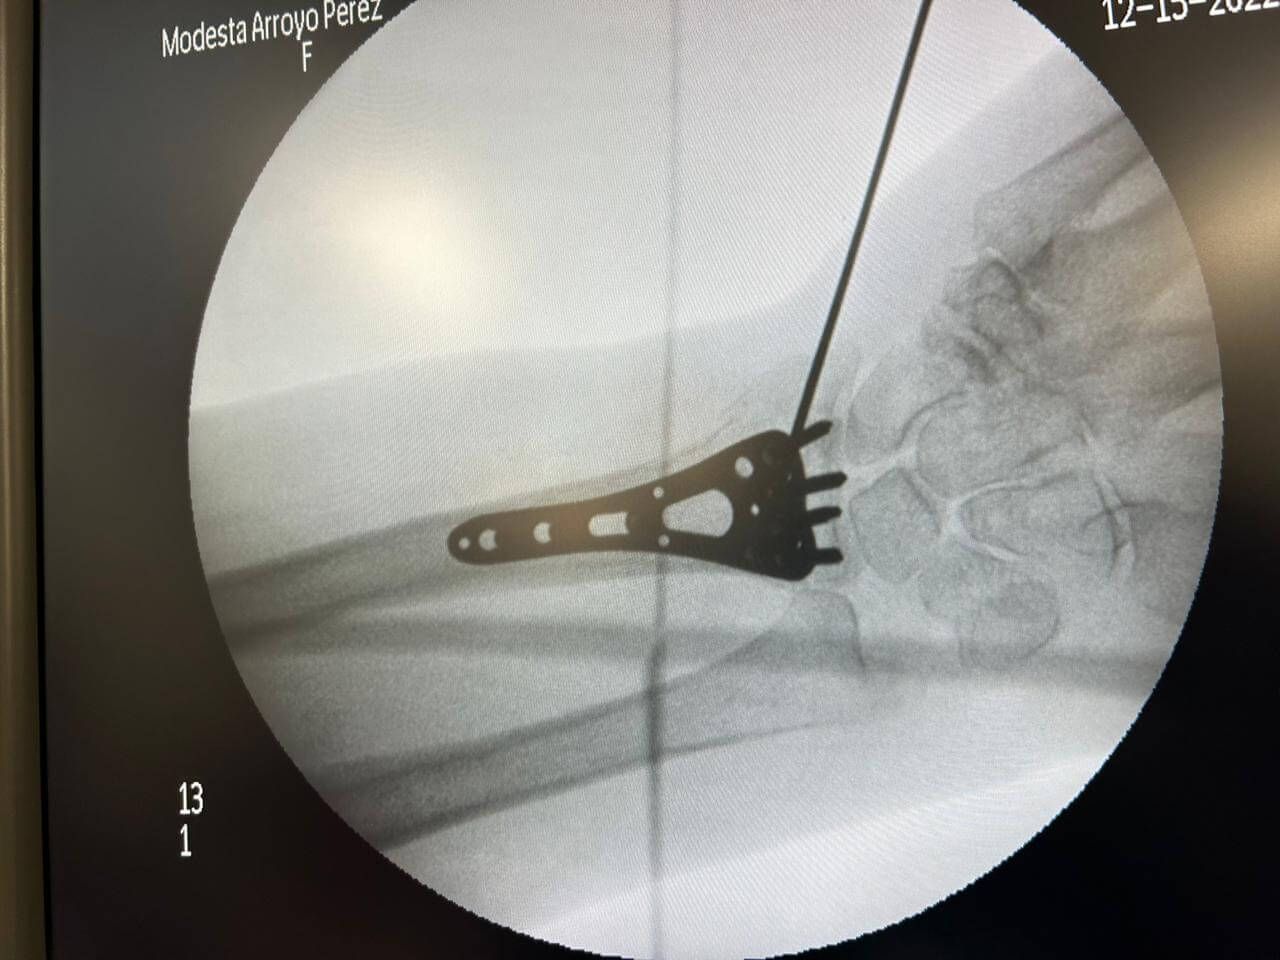

Cirugía de pie con mínima invasión

Enfocado en abordajes menos invasivos para tratar afecciones del pie.

Tratamiento de lesiones:

- Fracturas